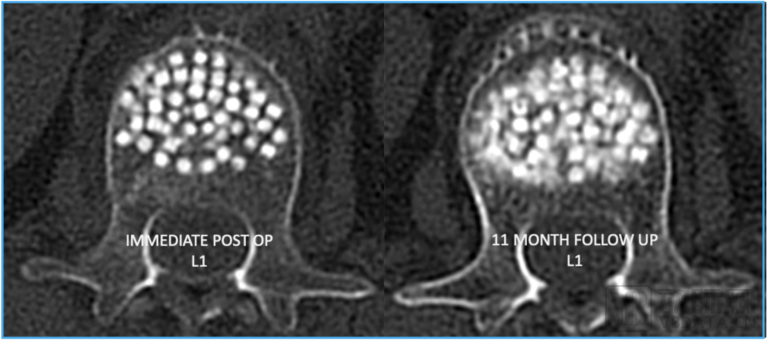

图片

右图为 OsteoPearl 植入物11个月后的情况 边缘模糊的部分显示了新骨正在最需要的地方形成

OsteoPearl VBA系统的专利工具——Elevoss腔体创建器,允许医生在处理椎骨损伤或骨折时,能够精确控制操作方向,并通过触觉反馈来感知操作情况,以便在患者体内准确地创建一个适合放置 OsteoPearl 植入物的空腔。OsteoPearl植入物由100%的皮质骨珠链组成,一旦重新水化,珠链会扩张40%,增加其体积和弹性,同时保持强度,从而更好地适应椎骨的形状并提供支持。